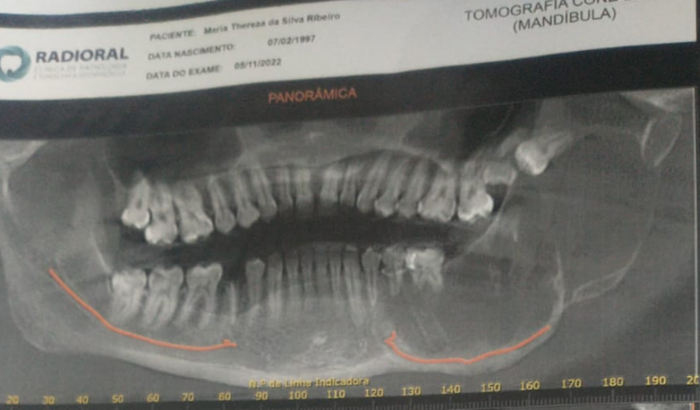

Olá, me Chamo Maria Thereza, faço um tratamento de um tumor na mandíbula chamado ameloblastoma, que infelizmente já destruiu todo o lado esquerdo do meu rosto. Preciso fazer dois cirurgias no hospital dos servidores do RJ, será tirado um osso da perna para enxertar no meu rosto e estamos tendo problemas com o TFD (trasporte fora de domicílio).